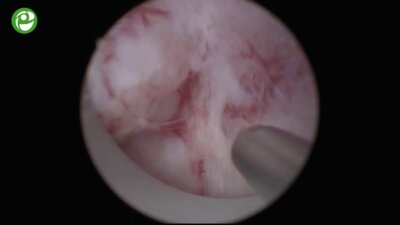

Конференция с международным участием «Высокие технологии в урологии»

06-08 апр 2017